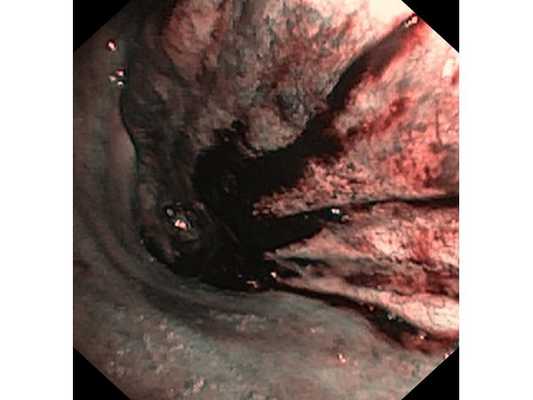

Первым этапом пациенту была проведена фибробронхоскопия, по данным которой выявлено, что устье нижнедолевого бронха слева сужено за счёт подслизистого и перибронхиального распространения опухоли.

Выполнена многократная биопсия из устья нижнедолевого бронха слева. По данным гистологического исследования материала эндоскопической биопсии верифицирован диагноз немелкоклеточного рака лёгкого.

- Эндоскопия бронхов. С целью визуального обнаружения опухоли, уточнения ее границ и забора опухолевой ткани производится бронхоскопия с биопсией. В 70-80% случаях информативным оказывается анализ мокроты на атипичные клетки, цитологическое исследование смыва с бронхов.